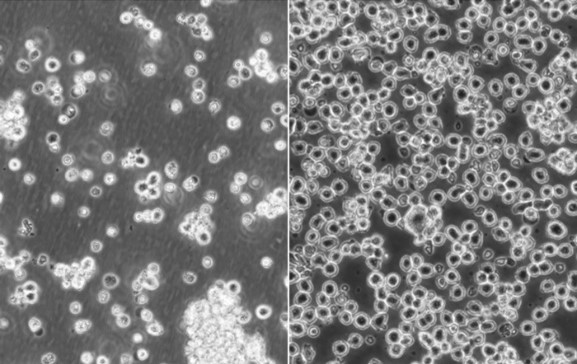

◆血淋巴细胞癌细胞系 - KMS-26 (JCRB1187)

| ● 小圆细胞形态 ● 部分为多核细胞 ● 遗传学 t(4;14)(p16.3;32.3), t(14;16)(q32.3;q23) ● 骨髓瘤,50岁,男性, 细胞系建立于2000年 参考文献 Pubmed id:14692515 Effects of all-trans retinoic acid (ATRA) on humanmyeloma cells. Otsuki T, Sakaguchi H, Hatayama T, Wu P, Takata A, Hyodoh F Leuk Lymphoma. 2003 Oct;44(10):1651-6 |